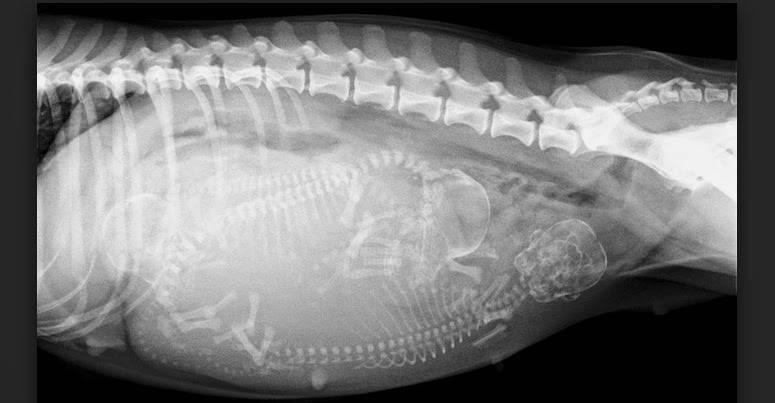

В этот период хозяину нужно быть начеку, так как щенки могут появиться на свет в любую минуту. Костная ткань у щенков уже очень прочная, зубы сформированы, рост соответствует размеру новорожденных. УЗИ позволит точно определить количество плодов.

Зародыши теперь четко видны на УЗИ, потому что их скелет к этому моменту уже полностью сформирован. Они также начинают пинаться. Живот матери к этому моменту уже почти облысел, чтобы, родившись, щенки могли легко найти, откуда пить молоко. Последние несколько недель довольно трудны для матери, плоды активно растут, занимая внутри слишком много места. По этой же причине ей трудно есть, поэтому «концентрированное» питание рекомендуется для нее на этой стадии беременности.

К восьмой неделе скелет щенков должен быть полностью сформирован. В это время ваш ветеринар может сделать рентген, чтобы подтвердить точный размер помета. Тем не менее, эта процедура может быть слишком инвазивной, и вам и вашему ветеринару решать, нужна она или нет.

Примерно на 50-й день скелет плода полностью затвердеет. Вы можете запросить рентген, чтобы подтвердить размер вашего помета, но ваш ветеринар может посоветовать вам не делать этого, потому что это слишком инвазивно и не нужно.